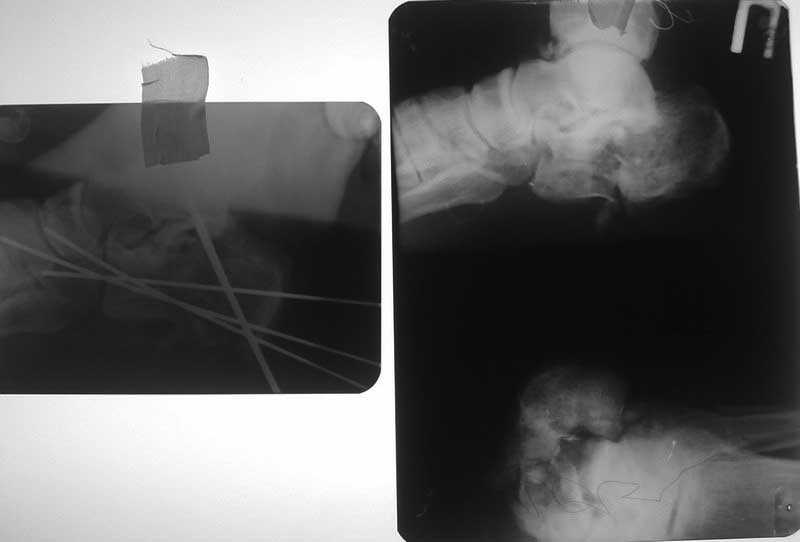

Здравствуйте уважаемые коллеги, прошу поделиться опытом лечения подобных повреждений.Пациент П. 40 лет пострадал в результате ДТП 30 07 12, в ургентном порядке – ПХО (рана ушита?!), гипсовая иммобилизация. К нам в клинику переведен 3 08 12 с диагнозом: Открытый 3ст. оскольчатый перелом правой пяточной кости со смещением, перелом м.берцовой кости в н/3, повреждение a.tibialis post.

Проведена ХО, репозиция перелома, фиксация спицами, 4 08 12 наладили постоянное вакуумирование с этапными некрэктомиями и перевязками каждые 48 ч. На сегодняшний день имеем такую картину, подумываем о декортикации фрагмента пяточной кости и продолжить вакуумирование. Что может посоветовать уважаемое сообщество?